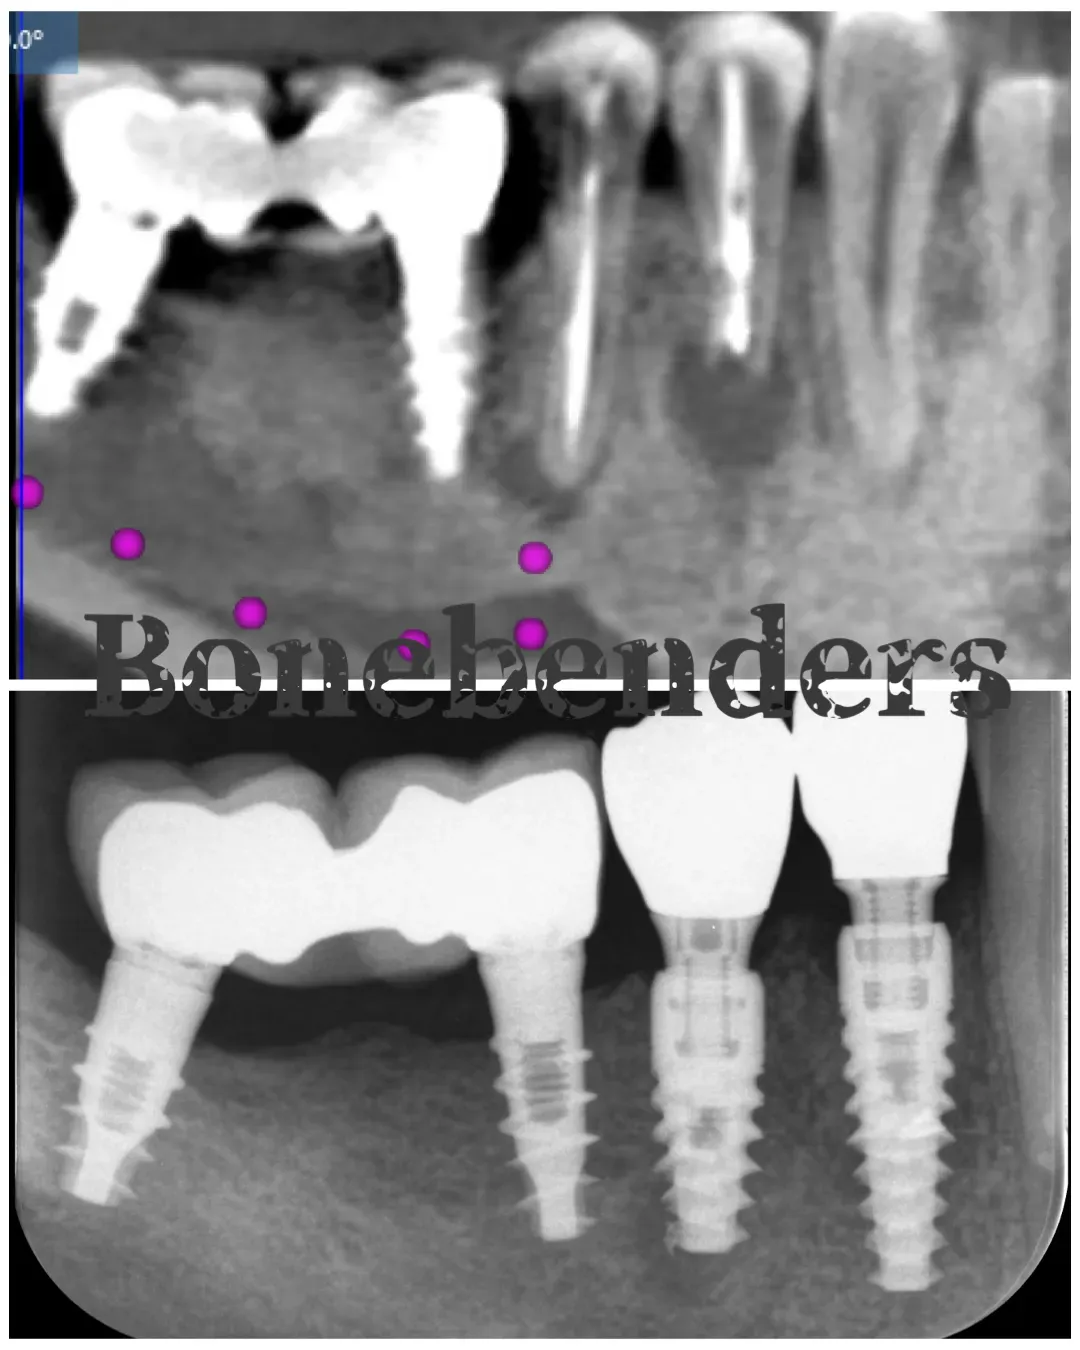

Il primo premolare aveva perso totalmente la parete ossea buccale, come evidenziato dalla sezione della CBCT qui sotto.

CBCT (Cone Beam CT) pre-operatoria che mostra le estese lesioni ossee dei due premolari inferiori di destra e il ponte su impianti che avevo inserito dieci anni prima.

Perdita totale della parete ossea buccale del primo premolare (sezione di CBCT).